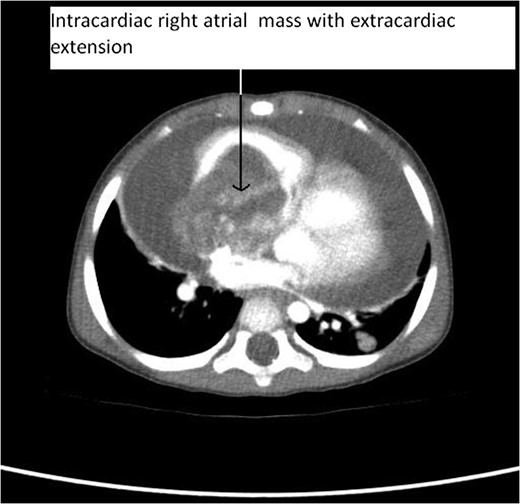

Primary cardiac tumour is a rare entity as secondaries in the heart are more common. A 2-year-old child was having repeated respiratory tract infection with poor oral intake and poor activity for 3 months. His symptoms progressed from New York Heart Association (NYHA) Class II to IV. On evaluation he had an intracardiac mass with extracardiac extension. Emergency tumour excision under deep hypothermic circulatory arrest was performed with provisional diagnosis of sarcoma. But Serum markers, histopathological examination and immunohistochemistry confirmed diagnosis of yolk sac tumour. Postoperative recovery was uneventful and the child was receiving adjuvant chemotherapy. Extensive literature review revealed only four cases of primary intracardiac yolk sac tumour published till date. Our case report is unique, in that intracardiac tumour had extracardiac extension by infiltration through right atrial wall. Previous four reports mention purely intracardiac mass.

CT Thorax showing intracardiac right atrial mass with extracardiac extension.

Our case report is unique, in that intracardiac tumour had extracardiac extension by infiltration through right atrial wall. Previous four reports mention purely intracardiac mass. The rarity in the literature of such pathological occurrence makes our case report very unique.